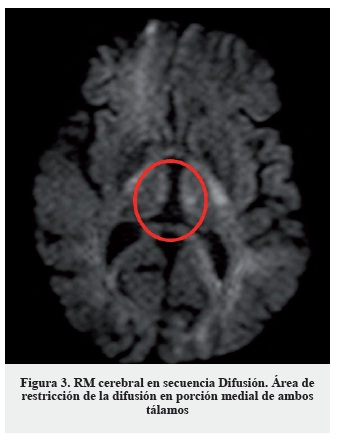

La clínica, los hallazgos en la exploración neurológica y el antecedente de cirugía resectiva gastrointestinal hacen sospechar como primera posibilidad diagnóstica una encefalopatía de Wernicke, probablemente desencadenada en el contexto de vómitos y administración de suero glucosado. Dada la alta morbimortalidad del cuadro se inició de forma urgente tratamiento sustitutivo con tiamina (vitamina B1) 300 mg intramuscular, asociada a cianocobalamina (vitamina B12) y piridoxina (vitamina B6) parenterales. No se pudo realizar determinación de niveles séricos de vitamina B1 previa a la administración del tratamiento de reposición. El tratamiento se instauró de forma diaria durante diez días, objetivando una mejoría sintomática a las veinticuatro horas tras la primera dosis, progresiva. Como única prueba complementaria se solicitó un estudio de neuroimagen con RM cerebral (secuencias habituales, difusión y secuencias dinámicas tras la administración de contraste intravenoso (gadolinio)) en la que se apreció hiperseñal simétrica en secuencias T2 y Flair de la porción medial de ambos tálamos (Figura 1), cuerpos mamilares y sustancia gris periacueductal (Figura 2), que se acompaña de una restricción de la difusión en la porción medial de ambos tálamos (Figura 3); además se evidenció hiposeñal simétrica y bilateral de ambos núcleos pálidos; todo ello compatible con encefalopatía de Wernicke.

Se señalan en las imágenes dichos hallazgos. Los hallazgos de resonancia magnética, si bien son poco sensibles (53%), son altamente específicos (93%), e incluso se señalan como patognomónicos en algunos manuales/artículos publicados, por lo que el diagnóstico diferencial no se establece con base en estos hallazgos. No es posible recoger imágenes de mayor resolución, pues estas han sido obtenidas directamente del programa utilizado por los radiólogos del hospital.